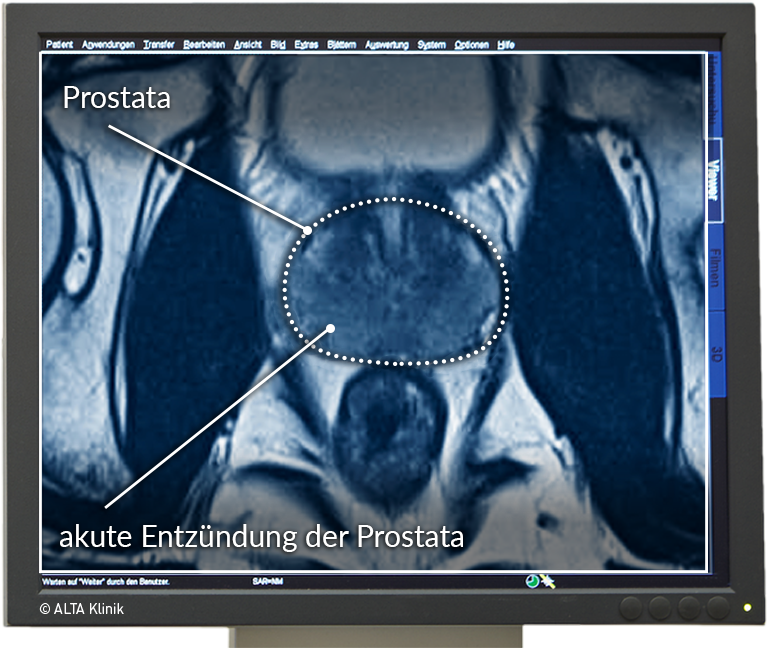

Sichere Prostatavorsorge mittels MRT-Untersuchung der Prostata Erstmals Geburt im MRT aufgenommen

Multiparametric MRI of the Prostate – ALTA Klinik MRT อิสรภาพ ลัดเลาะกินเที่ยวร้านเด็ดใกล้สถานีรถไฟฟ้าย่านฝั่งธน | Becquetwinery

Prostata MRT – die sichere und schmerzfreie Alternative zur Biopsie MRT อิสรภาพ ลัดเลาะกินเที่ยวร้านเด็ดใกล้สถานีรถไฟฟ้าย่านฝั่งธน | Becquetwinery